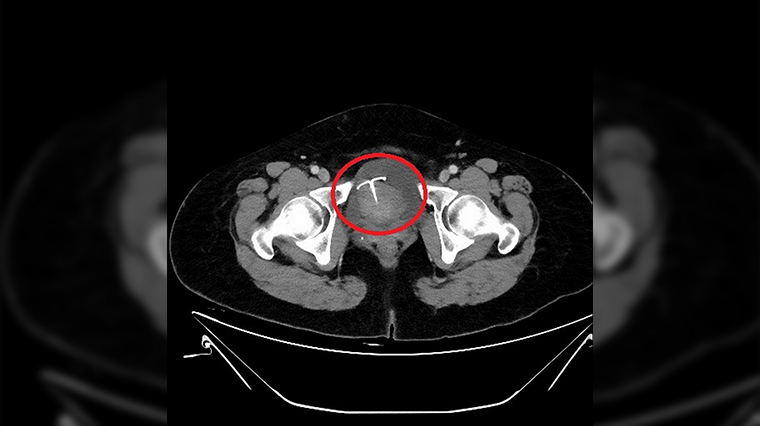

【NOW健康 連珮妤/新北報導】55歲的張女士日前因腹痛1個多月,本以為是腸胃症狀,至地方診所看診服藥後仍舊疼痛不止,遂至台北慈濟醫院婦產部門診就醫,經超音波檢查後發現竟是放置10餘年的銅製避孕器穿透子宮,引起腹腔嚴重發炎感染,且出現小腸沾黏,邱筱宸醫師以電腦斷層確認避孕器的確切位置後,執行子宮開腹切除術將子宮摘除,並仔細清理子宮及小腸的沾黏情況,術後病人恢復良好順利出院。

▲電腦斷層影像顯示避孕器已經穿透子宮,須執行子宮開腹切除術將子宮摘除。(圖/台北慈濟醫院提供)

根據統計,子宮內避孕器約有千分之8的機率會排出體外,甚至有千分之2的機率會穿破子宮掉入腹腔,導致腹痛、發炎,引發腸沾黏的問題發生。邱筱宸醫師表示,子宮避孕器會穿透子宮,並非裝設時的問題,而是避孕器對子宮來說是1種「異物」,無法完全貼合子宮的立體空間,所以身體會排斥它,因此避孕器容易透過子宮進入腹腔裡,掉出的避孕器若卡在患者膀胱,會產生血尿,而掉進腹腔也可能引發化膿發炎,嚴重甚至會造成敗血症和腹膜炎。